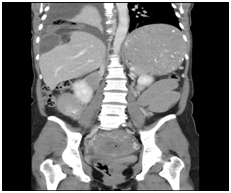

Case patient developed two episodes of large (200ml) green vomit 24hours after the caesarean section. On review, her epigastria pain improved after the delivery but nausea remained. The vomit was brought on by food. Bowel sound was absent on abdominal examination. The abdomen was generally soft and appropriately tender to what one would expect soon after a caesarean operation. A plain abdominal radiograph (AXR) revealed dilated loops of small bowel indicating post-operative ileus. Input from the general surgeons was sought on day two post-op which recommended nasogastric tube (NGT) decompression with free drainage. Chest radiograph (CXR) was ordered to confirm correct position of the NGT. Interestingly, the NGT still remained coiled in the oesophagus on the second CXR see Figure 1 after being repositioned. Despite of this, the NGT was draining stomach content freely and a decision was made not to subject the functional NGT from further repositioning. Case patient’s symptoms did not improve after 24 hours of drainage, therefore a repeat AXR with gastrograffin study see Figure 2 was organised which suggested the possibility of a small bowel obstruction. An abdominal computed tomography (CT) was arranged to confirm and locate the small bowel obstruction. It showed the presence of abdominal content in the right sided chest through a diaphragmatic defect see Figure 3. A right sided non-strangulated diagrammatic hernia was diagnosed. The general surgeons performed an emergency laparoscopic right sided diaphragmatic hernia repair and returned the incarcerated bowel to the abdomen. Upon direct visualisation, 20cm of terminal ileum was herniated through a 6cm defect on the right diaphragm. The defect was approximated and sutured with four interrupted size 0 monofilament nylon sutures. The case patient recovered well after the operation and was discharged home 5 days after with a healthy baby girl.

Figure 3 CT abdomen - There is a diaphragmatic hernia on the right containing loops of small bowel and associated with a right pleural effusion. It is associated with a small bowel obstruction. The colon is not distended. The stomach is grossly distended. Features are consistent with a right sided diaphragmatic hernia with small bowel obstruction.